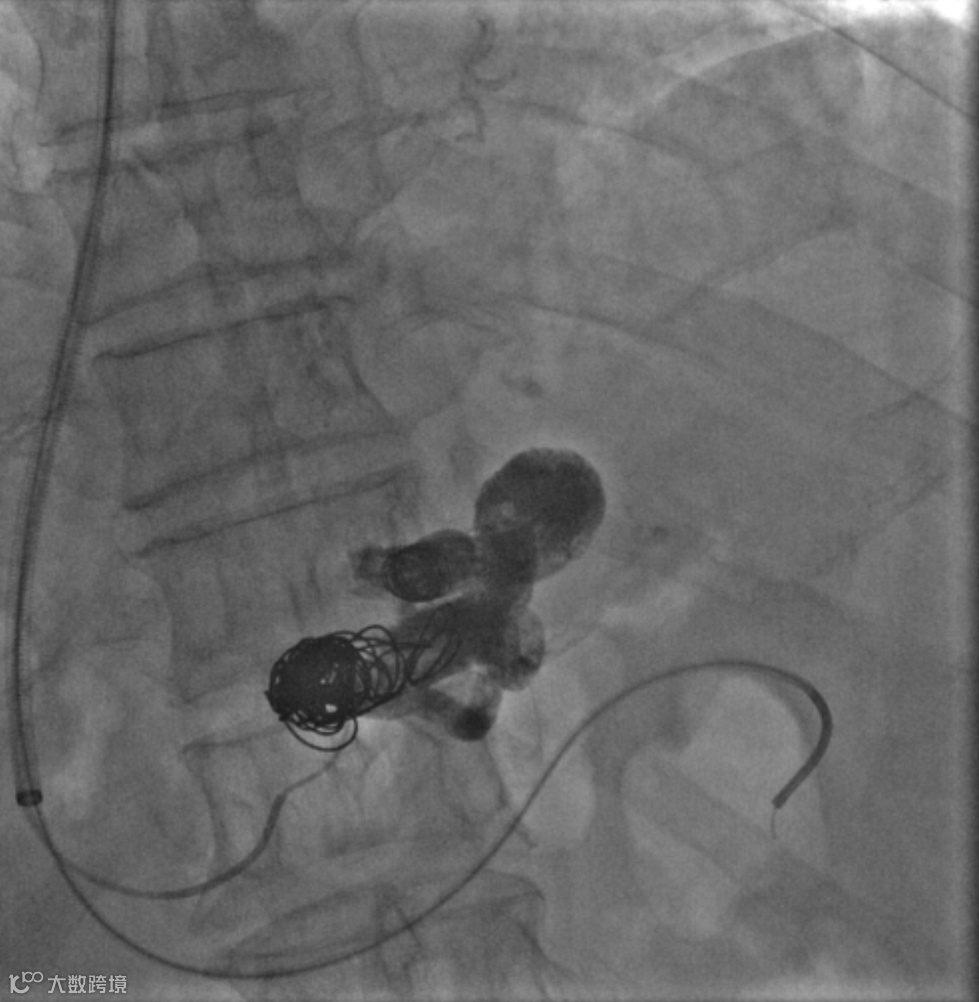

经右颈内静脉穿刺门静脉右支后行造影

超选择插入至曲张静脉,注入弹簧圈栓塞

超选择插入至曲张静脉,经微导管注入格鲁巴胶至曲张静脉血流基本停滞

术后造影(即刻效果):曲张静脉血管网未见显影